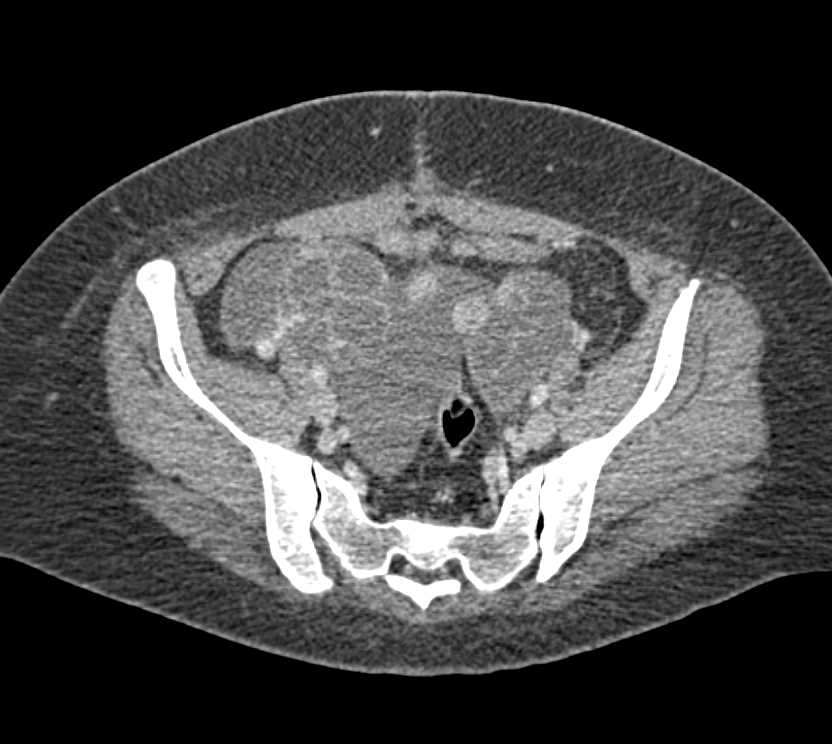

CASE NUMBER 288

Ovarian Cystadenocarcinoma